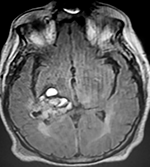

EJEMPLO DE CASO CLÍNICO (8)

Paciente femenino de 29 años de edad con historial de cefalea crónica que presenta súbitamente disdiadococinesia y dismetría izquierda.

El estudio de RMN presenta una lesión bien circunscrita en hemisferio cerebeloso izquierdo con periferia de predominio hiperintenso en T1 y T2, y centro hipointenso, edema perilesional mínimo, así como una imagen de un vaso venoso alimentador que recorre hacia el ángulo pontocerebeloso izquierdo.

Se realizó una craniectomía suboccipital paramedial derecha, así como un abordaje transcortical en el hemisferio cerebeloso izquierdo llegando a la región perilesional de aspecto amarillento, posteriormente se observa una lesión oscuro-verdoso de contenido hemático antiguo, retirando la cápsula y su contenido en la totalidad.

La evolución clínica de la paciente fue satisfactoria solo preservando la dismetría como secuela.

El resultado histopatológico fue consistente en angioma cavernoso.

El estudio de control de RMN se observa la brecha quirúrgica y ausencia de lesión (figs. 1, 2 y 3).

Figura 1:

Lesión cerebelosa izquierda ponderaciones en T1 y T2, la flecha señala vaso nutricio hacia el ángulo pontocerebeloso izquierdo, se puede observar el centro de intensidad heterogénea con contenido quístico multiloculado y edema perilesional leve.